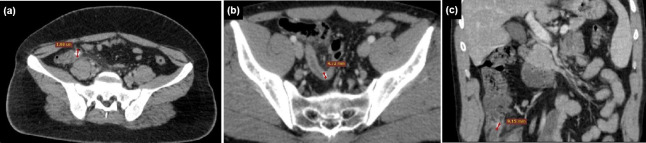

Methods: Between January 2020 and January 2023, 294 patients diagnosed with AA were retrospectively analyzed. Of these, 140 (47.6%) had appendicoliths (Group 1), and 154 (52.4%) did not (Group 2). CT findings of AA and CTAS were evaluated. CBC parameters, CRP levels, and SII scores were compared between the groups, and the presence of appendix perforation was analyzed.

Results: The mean diameter and wall thickness of the appendix, presence of intra-abdominal fluid, and severity of periappendi-ceal fat stranding were higher in Group 1 (p<0.001, p=0.024, p=0.009, p<0.001, respectively). The CTAS was also higher in Group 1 (7.51±2.35) compared to Group 2 (6.38±2.41; p<0.001). There was a positive correlation between the diameter of the appendicolith and CTAS (rho=0.450, p<0.001). In Group 1, CTAS was higher in patients with more than one appendicolith (p=0.003). Perforation was observed in 15 patients (10.7%) in Group 1 and five patients (3.2%) in Group 2, with a higher incidence in Group 1 (p=0.011). Among Group 1 patients, the perforation rate was higher in those with more than one appendicolith (p=0.019). The mean CTAS was higher in patients with appendiceal perforation (10±1.13) compared to those without perforation (7.22±2.29) (p<0.001). Monocyte (MONO) counts were also higher in Group 1 (p=0.002). Other CBC parameters, CRP levels, and SII scores did not differ significantly between Groups 1 and 2 (p>0.05). However, CRP levels and MONO counts were elevated in patients with perforated appendicitis (p<0.001 and p=0.026, respectively).

Conclusion: Acute appendicitis with appendicoliths is associated with more pronounced inflammation and a higher rate of perforation. CTAS, CRP, and MONO levels tended to be elevated in cases of appendiceal perforation. A comprehensive evaluation incorporating the presence of appendicoliths, CTAS, and laboratory parameters may provide valuable insights into the severity of inflammation in AA.